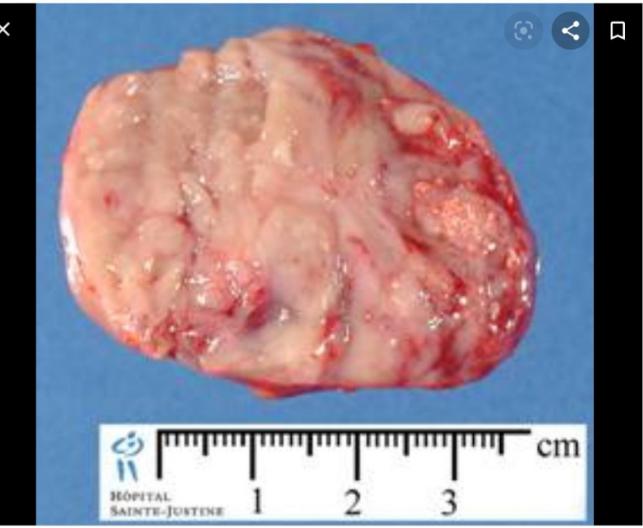

Макропрепарат: пухлина білого або біло-сірого кольору, з множинними ділянками крововиливів, некрозів і кістами, що характеризують часткову резорбцію некротичного детриту. Пухлина досить інтенсивно проростає в м'які тканини, даючи локальні ускладнення в вигляді проростання в судини з кровотечею, тромбозів і вторинних васкулярних некрозів.